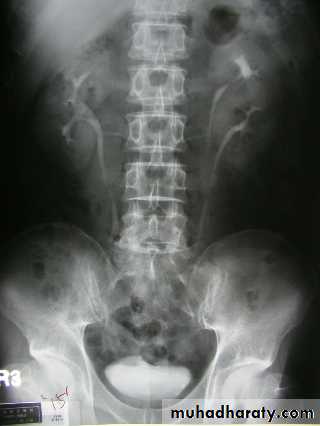

Horseshoe kidney:

• The kidneys fail to separate and they are almost invariably joined at their lower poles.

• Causes increase incidence of PUJ obstruction and stones formation.